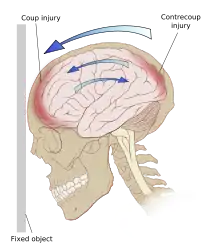

Even in the absence of an impact, significant acceleration or deceleration of the head can cause TBI; however in most cases, a combination of impact and acceleration is probably to blame.[37] Forces involving the head striking or being struck by something, termed contact or impact loading, are the cause of most focal injuries, and movement of the brain within the skull, termed noncontact or inertial loading, usually causes diffuse injuries.[20] The violent shaking of an infant that causes shaken baby syndrome commonly manifests as diffuse injury.[67] In impact loading, the force sends shock waves through the skull and brain, resulting in tissue damage.[37] Shock waves caused by penetrating injuries can also destroy tissue along the path of a projectile, compounding the damage caused by the missile itself.[23]

Damage may occur directly under the site of impact, or it may occur on the side opposite the impact (coup and contrecoup injury, respectively).[66] When a moving object impacts the stationary head, coup injuries are typical,[68] while contrecoup injuries are usually produced when the moving head strikes a stationary object.[69]